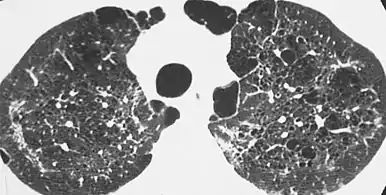

| CT scan of the lung showing bullae in the lower lung lobes of a subject with type alpha-1-antitrypsin deficiency. There is also increased lung density in areas with compression of lung tissue by the bullae. | |

A focal lung pneumatosis, is an enclosed pocket of air or gas in the lung and includes blebs, bullae, pulmonary cysts, and lung cavities. Blebs and bullae can be classified by their wall thickness.[1]

- A bulla has a wall thickness of less than 1 mm.[2] By radiology definition, it has a total size of greater than 1 cm.[3] By pathology definition, it originates in the lung parenchyma (rather than in the pleurae).[4]